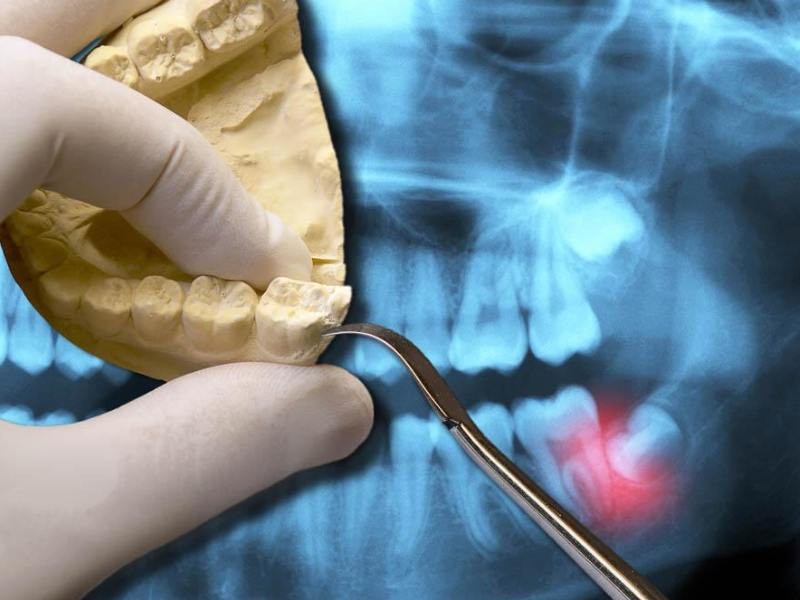

As cirurgias orais para extração dos sisos, também conhecidos como terceiros molares, são procedimentos comuns na odontologia. Os sisos costumam nascer entre os 17 e 25 anos, mas muitas vezes não têm espaço suficiente na arcada dentária, podendo causar dor, inflamação, desalinhamento dos dentes ou infecções. A extração pode ser indicada mesmo antes de surgirem sintomas, como forma de prevenção. O procedimento é feito com anestesia local e, com os cuidados pós-operatórios adequados, a recuperação costuma ser tranquila e rápida.